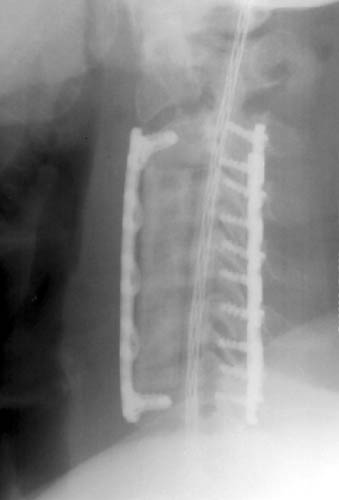

Lateral radiograph demonstrating the strut graft now is displaced

anteriorly, and the

inferior fixation screw is not located in the vertebral body. No acute fracture

seen. |